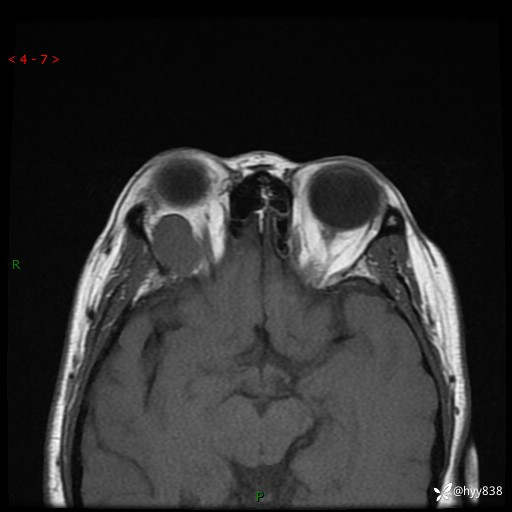

老年女性,右眼球突出1月。说说鉴别诊断,看谁第一个秒---(有结果)

主诉:发现右眼球突出1月余

简要病史:患者于1月前无明显诱因发现右眼球突出,偶感磨痛、眼胀,无视力下降,无头痛,恶心呕吐等不适。10天前就诊于当地县人民医院就诊,完善头颅ct检查,诊断为右侧眼眶肿物,建议患者上级医院进一步治疗,患者因个人原因拒绝。拟行手术,来我院就诊,门诊行相关检查后以“右眼眼眶肿物”收入院。 患病以来,患者精神饮食睡眠尚可,大小便如常、体重无明显改变。

辅助检查:MRI

临床诊断:眼眶肿物

眼眶MRI平扫+增强